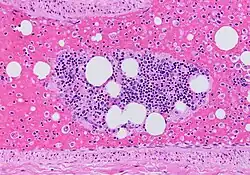

| Microscopic section of the lungs showing a blood vessel with fibrinoid material and an empty space indicative of the presence of lipid dissolved during the staining process. Haematoxylin and eosin stain | |

Once fat emboli enter the blood circulation, they can lodge at various sites of the body, most commonly in the lungs (up to 75% of cases). However, it can also enter the brain, skin, eyes, kidneys, liver, and heart circulation, causing capillary damage, and subsequently cause organ damage in these areas. There are two theories that describe the formation of a fat embolus:[6]